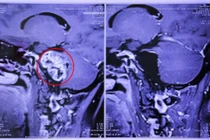

Bệnh nhân P.T.N, 73 tuổi, ngụ tại phường Tam Bình, TP HCM, được phát hiện khối u màng não thái dương trái kích thước 3,5x5cm sau khi đi khám vì triệu chứng đau đầu kéo dài.

Trước đó, bệnh nhân chỉ có biểu hiện đau đầu nhẹ và được điều trị giảm đau thông thường không hiệu quả. Đến khi bị té ngã trong lúc tắm, gia đình đưa bà đến Bệnh viện Đa khoa Thủ Đức thăm khám. Qua chụp CT và MRI, các bác sĩ phát hiện khối u màng não đáng ngại, vị trí sàn sọ phức tạp cần can thiệp phẫu thuật.

Hình ảnh khối u trên phim chụp - Ảnh BVCC